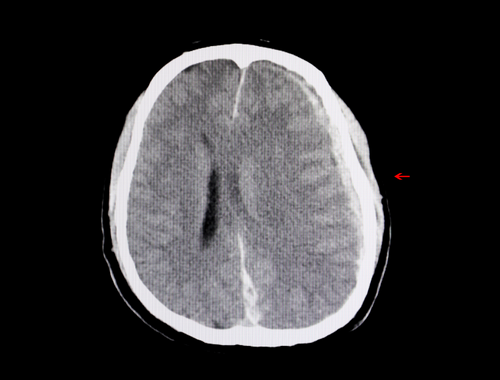

A CT scan and MRI will show that there is a hematoma in the brain.

A chronic subdural hematoma can be diagnosed using the same imaging tests as for an acute subdural hematoma, namely a CT scan and MRI. Using contrast with the CT scan is sometimes needed for diagnosing slow bleeds in the brain.